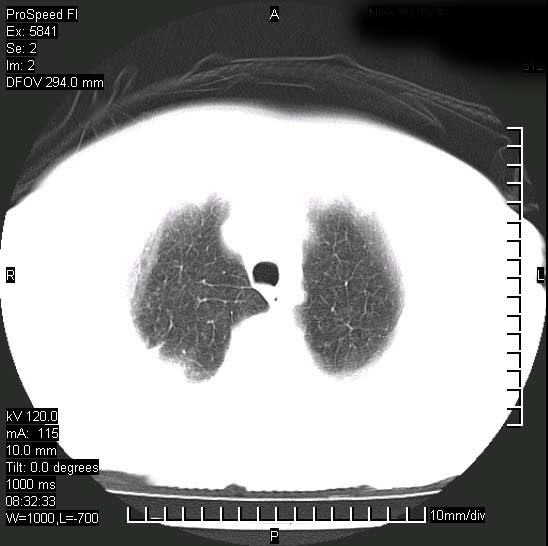

胸痛,咳嗽,气短一周,无发热。右上肺见一结节灶,边缘刺角,内见多个小钙化结节。考虑结核球?肿瘤? 余无异常没有上传。

考虑右肺上叶继发性肺结核,结核球形成。

考虑结核球,并胸膜局限性增厚!!